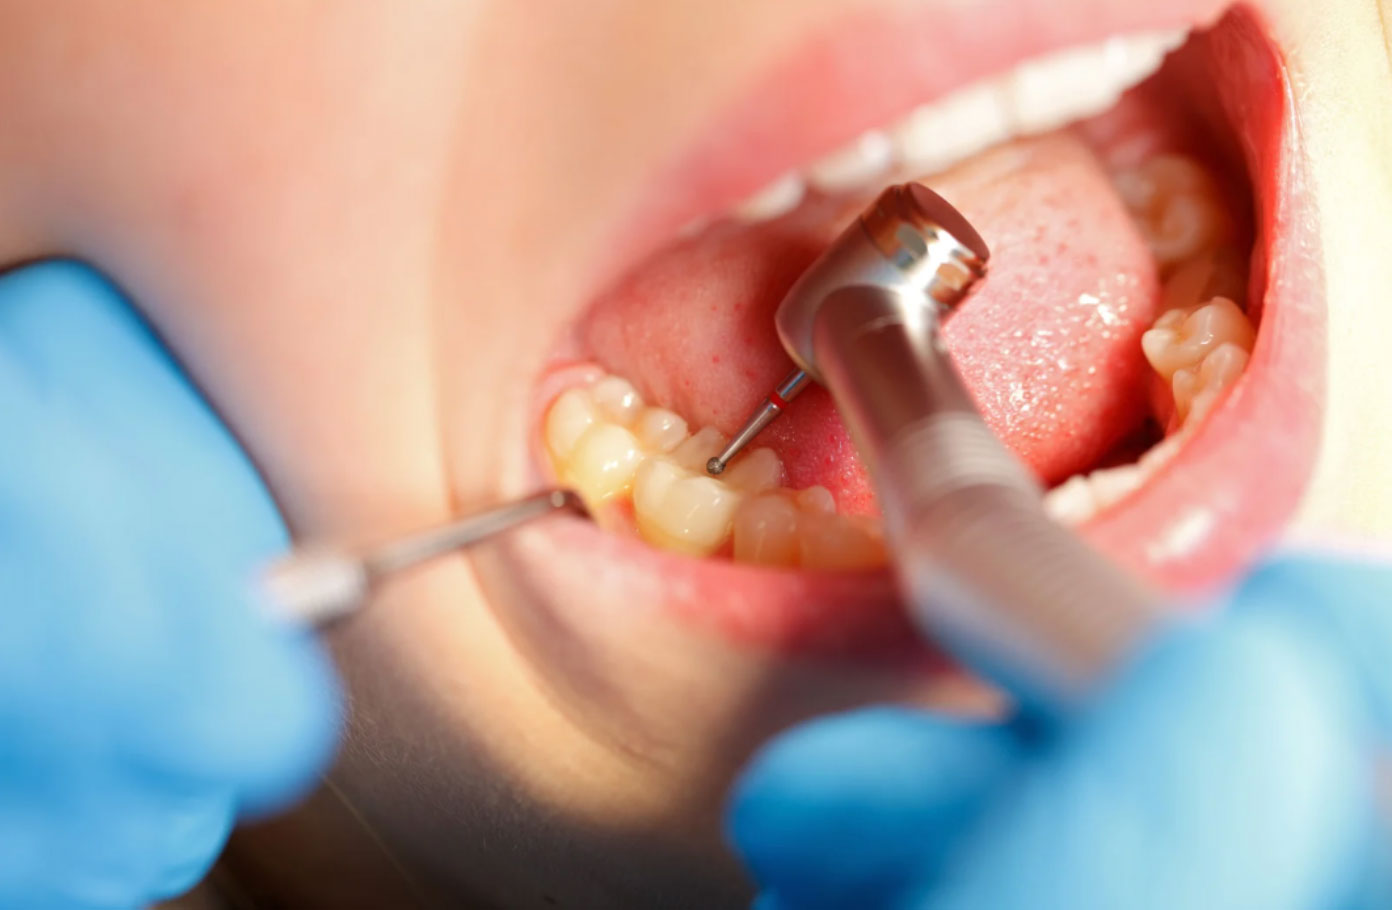

Durante o procedimento, o dentista remove a parte comprometida do dente, higieniza a região e preenche o espaço com um material restaurador, devolvendo ao dente sua forma original e sua capacidade de mastigação.

Como é Feito o Procedimento?

O processo de restauração do dente é rápido, seguro e praticamente indolor.

Veja como funciona:

- Avaliação clínica e radiográfica para diagnóstico e escolha do material ideal.

- Anestesia local, se necessário, para garantir conforto total durante o procedimento.

- Remoção da área comprometida (cárie, trinca, restauração antiga).

- Limpeza e preparo da cavidade.

- Escaneamento intraoral, se for realizada restauração indireta

- Aplicação do material restaurador com técnicas adesivas.

- Modelagem, ajuste da mordida e polimento, devolvendo forma e brilho ao dente.

Nas restaurações diretas é possível realizar o procedimento em uma única consulta, exceto se houver necessidade de restauração de vários dentes.